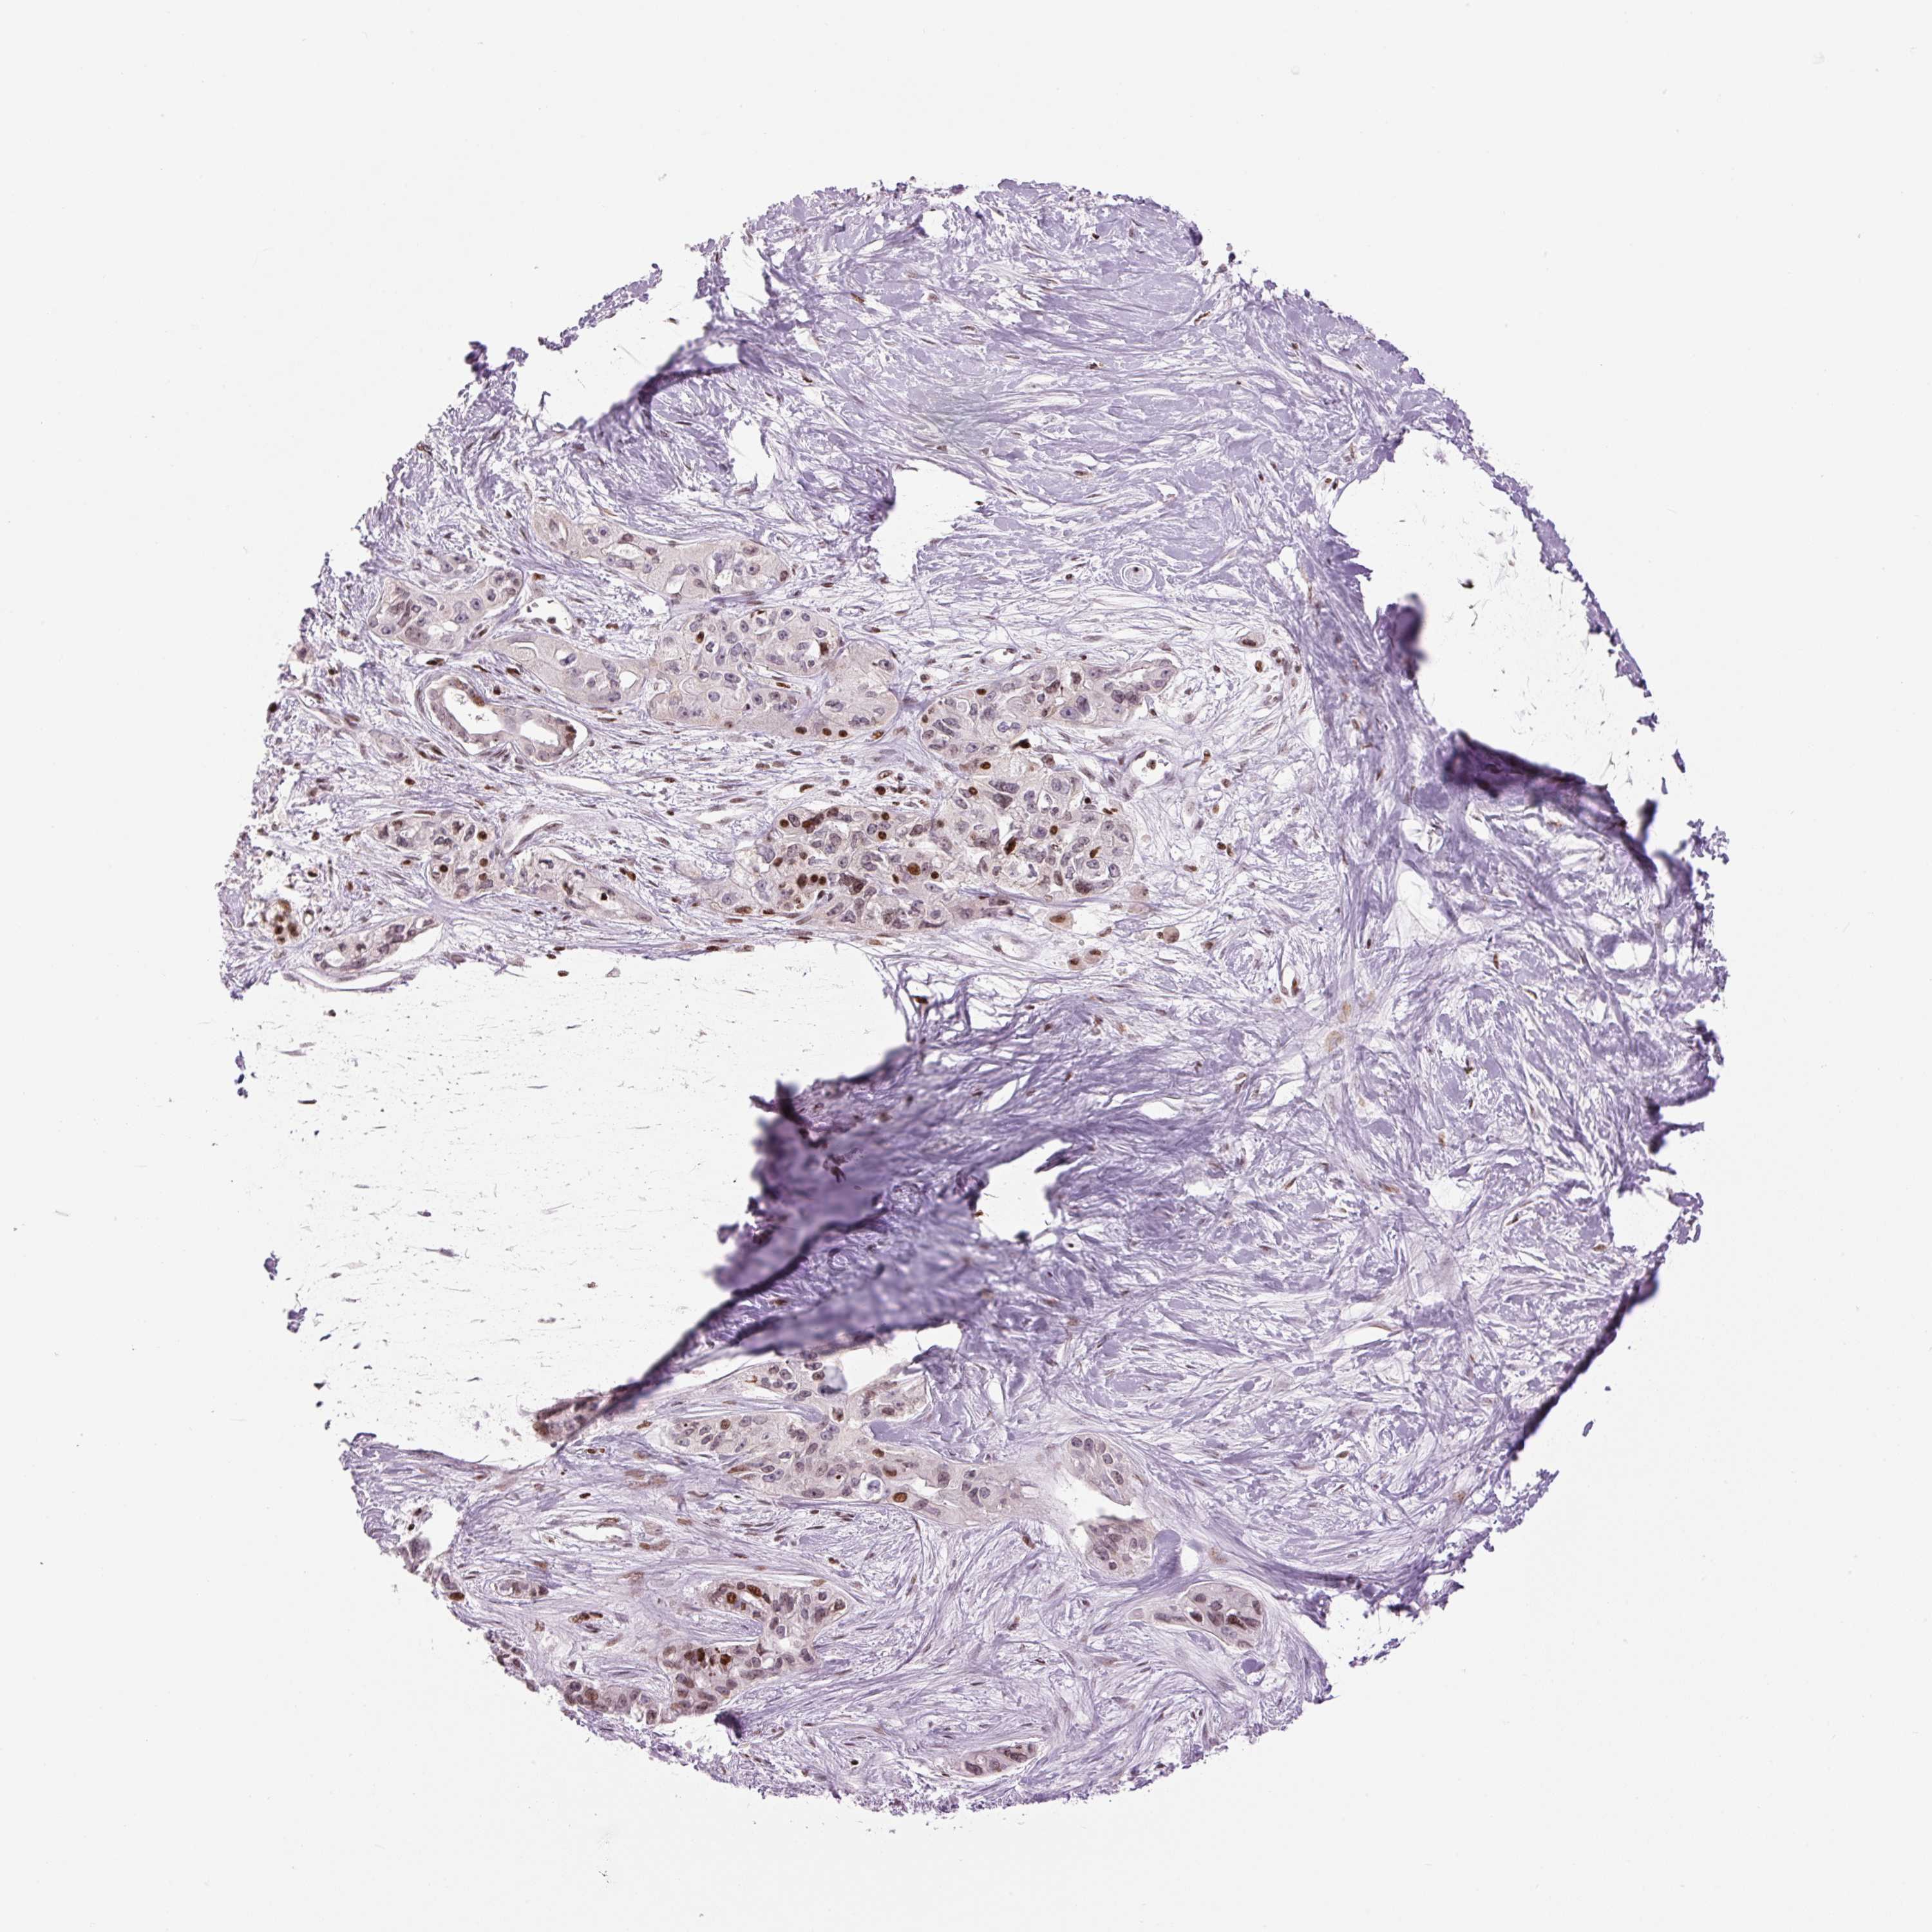

PANCREATIC CANCER - Protein expressioni

A mouse-over function shows sample information and annotation data. Click on an image to view it in a full screen mode. Samples can be filtered based on level of antibody staining by selecting one or several of the following categories: high, medium, low and not detected. The assay and annotation is described here.

Note that samples used for immunohistochemistry by the Human Protein Atlas do not correspond to samples in the TCGA dataset.

Antibody stainingi

Antibody staining in the annotated cell types in the current human tissue is reported as not detected, low, medium, or high, based on conventional immunohistochemistry profiling in selected tissues. This score is based on the combination of the staining intensity and fraction of stained cells.

Each image is clickable and will lead to virtual microscopy that enables deeper exploration of all samples and also displays staining intensity scores, fraction scores and subcellular localization as well as patient and tissue information for each sample.

Antibody HPA053816

Staining

High

Medium

Low

Not detected

Intensity

Strong

Moderate

Weak

Negative

Quantity

>75%

75%-25%

<25%

None

Location

Nuclear

Cytoplasmic/membranous

Cytoplasmic/membranous,nuclear

Adenocarcinoma, NOS